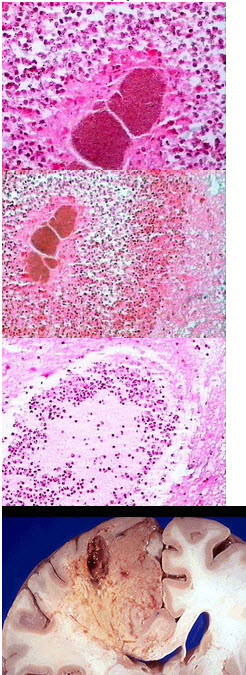

49、单项选择题

患者男性,42岁,持续性剧烈腹痛3小时伴恶心、呕吐,拟诊“急性阑尾炎”手术。术中见阑尾呈紫黑色,根部破裂。镜检如图,应诊断为()

A.急性蜂窝织性阑尾炎伴穿孔

B.坏疽性阑尾炎伴穿孔

C.慢性阑尾炎伴穿孔

D.阑尾脓肿

E.阑尾腺瘤

229、单项选择题

患者,女,8岁。因头痛呕吐,高热入院。大体观如图,镜下可见大量变性坏死中性粒细胞,如图所示。应诊断为()

A.流行性脑脊髓膜炎

244、单项选择题

死者,女性,68岁,长期胸闷不适,进行性加剧至心衰而亡。

对于该疾病的描述,错误的是()

270、单项选择题

某患者,烫伤半小时后入院,可见手臂多个大小不等的水疱。

该种炎症的常见发生部位,除了下列哪项以外()

287、单项选择题

患者,男,45岁。因高热、咳嗽、咳大量脓痰入院。X线示一有液平面的空腔。手术切除病变肺组织,巨检见病变中央呈囊腔状,腔内含黄色脓液,镜下腔壁可见大量变性坏死中性粒细胞,如图所示,可诊断为()

A.肺结核